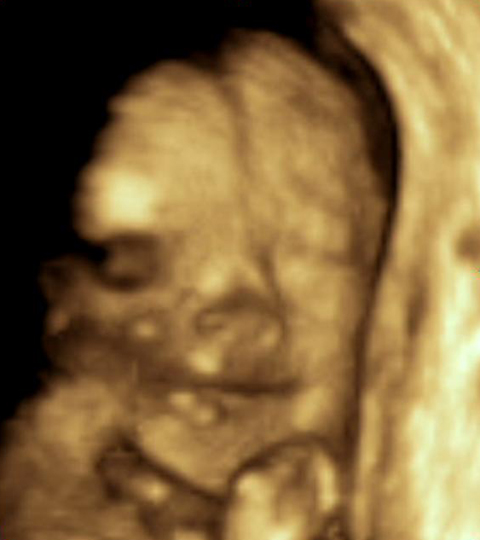

Un ultrasonido 3D usa un software más sofisticado para descifrar la imagen, produciendo una imagen tridimensional de la superficie del feto. Desde aquí, el médico puede medir la altura, el ancho y la profundidad del feto para diagnosticar cosas como labio leporino y defectos de la columna.

Más avanzado aún es un ultrasonido 4D. En la ecografía 4D, el software produce un video en tiempo real del feto para mostrar su movimiento, ya sea chuparse el dedo, abrir los ojos o estirarse. Esta exploración ofrece aún más información sobre el desarrollo del feto.